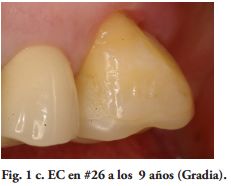

Al momento del examen, 10 (90.9%) EC estaban en función en 10 pacientes. Un molar 26, restaurado con EC, se perdió por enfermedad periodontal después de 12 años y 9 meses en función. Ninguna restauración se desprendió, no hubo recidiva de caries y al examen radiográfico no se observaron lesiones patológicas en los 10 DPET en función (Figs. 1a,1d; 2c; 3c,3d; 4c).

Dos pequeñas fracturas en crestas marginales distales fueron pulidas, sin afectar la restauración. El Éxito Clínico, relacionado a la calidad de las restauraciones, fue Excelente, 5 (50%), Bueno, 4 (40%) y Sobrevida Funcional, 1(10%) (Tabla 2).

Mientras, en estudios clínicos y de laboratorio, los cementos resinosos de polimerización química y dual, tuvieron un mejor comportamiento que los fotopolimerizables y los de autograbado (38-44). Sin embargo, utilizando unidades de curado LED de alta potencia y aumentando el tiempo de exposición, a través de materiales cerámicos con diferentes espesores, recientes investigaciones de laboratorio han encontrado mayor grado de conversión y después de 24 horas, mayores valores de microdureza, en cementos resinosos fotopolimerizables y duales (45,46). Por lo tanto, los procedimientos clínicos y los cementos utilizados, pudieron haber influido en el Éxito Clínico obtenido (90%) (Figs. 1c, 2b, 3b, 4b).